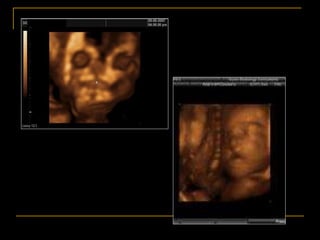

Embryology

AJR 2004; 183:229-235